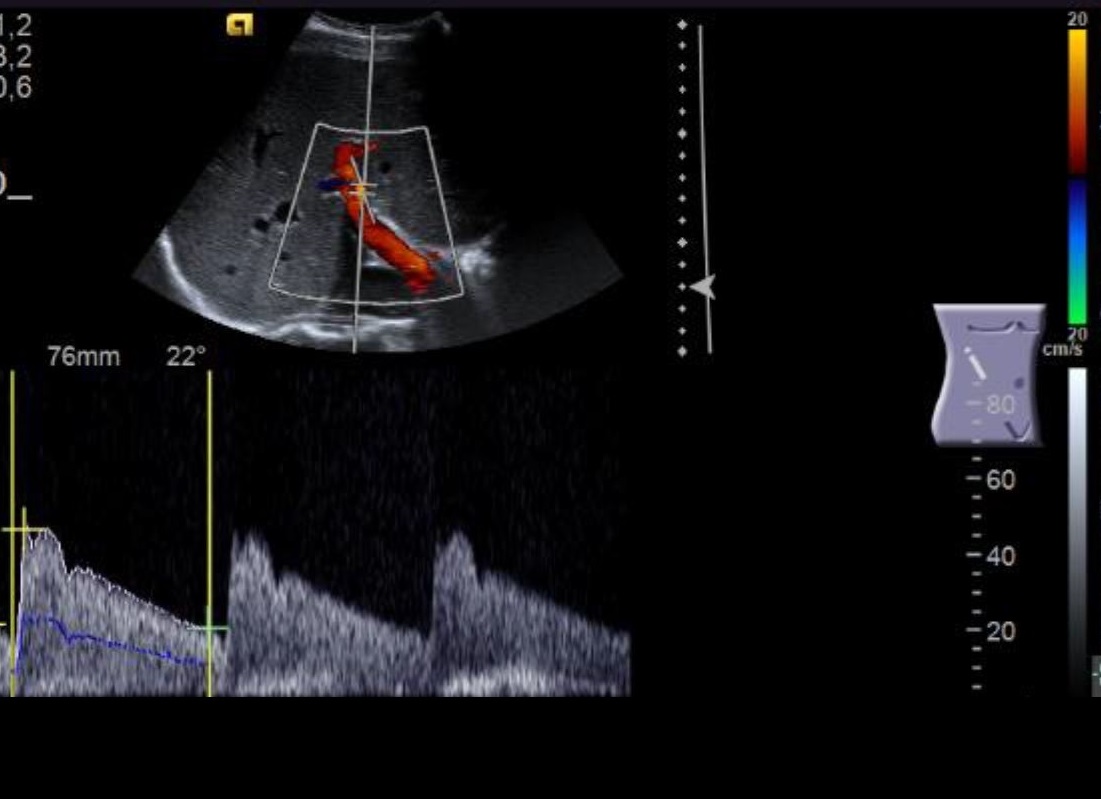

Zusätzlich erfolgt eine Beurteilung von Gefäßen: Hauptschlagader („Aorta“) und Hauptvene sowie die großen abgehenden Äste der Aorta (versorgende Arterien für Leber und Milz, die Nieren und den Darm). Auch die Durchblutung der Leber sowie der Nieren wird dargestellt und vermessen. Ferner können vergrößerte Lymphknoten erkannt werden.

Ultraschall der Leber mit Leberdurchblutung:

Aber der Ultraschall kann nicht nur verschiedene Gewebearten differenzieren, er kann auch ruhende von bewegten Strukturen unterscheiden. Hier kommt die „Doppler-Methode“ (nach dem österreichischen Physiker Christian Andreas Doppler) ins Spiel, mit der man z.B. fließendes Blut entdecken und sogar die Flussgeschwindigkeit messen kann: Das Signal verändert sich, je nachdem, ob und wie schnell der Blutstrom sich auf den Schallkopf zu oder von ihm wegbewegt. Dies wird durch eine Geräusch kodiert (Doppler-Sonographie) oder mit unterschiedlichen Farben belegt (Farbdoppler) – das ergibt dann die bekannten bunten Bilder.